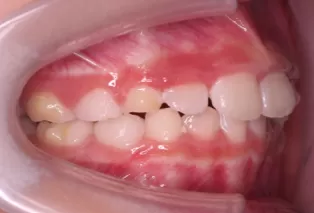

Photos intra-orales